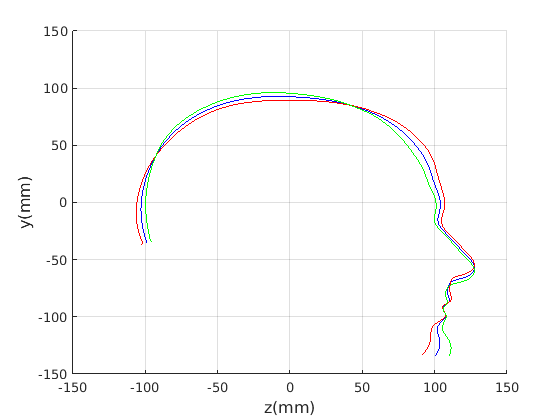

Figure 16 shows examples of the robust ellipse fit for four head profiles. The centre of the ellipse is used in a pose normalisation procedure where the ellipse centre is used as the origin of the profile and the angle from the ellipse centre to the nasion is fixed at -10 degrees. We call this Ellipse Centre - Nasion (ECN) pose normalisation and later compare this to GPA. The major and minor axes of the extracted ellipses are plotted as red and green lines respectively in Fig. 16.

|

Figure 17 shows all 100 profiles overlaid with the same alignment scheme. The median value of major ellipse axis and the ellipse centre-nasion angle differ by 3.6 degrees, so that when the nasion angle is fixed at -10 degrees, the median ellipse angle is -6.4 degrees (cf. -7.4 degrees with manual landmarking of the nasion). We noted regularity in the orientation of the fitted ellipse as is indicated by the clustering of the major (red) and minor (green) axes in Fig. 17 and the histogram of ellipse orientations in Fig. 18. For most people, the major axis of the ellipse is closely aligned with the y-axis (upright), and titled slightly forwards. A minority of heads (9%) in the training sample have their major ellipse axes closer to the vertical (these relatively tall and short heads are known as brachycephalic.) Ellipse axis clustering (relative to the fixed ellipse centre-nasion line) does not appear to be sharply defined. This is because many crania are close to circular in cross-section, making the orientation of these angles sensitive to small changes in shape from one person to the next. Note also the variation at the back of the head due to a variety of hair styles, some of which protrude from under the cap. We limit the region over which we model the cranial shape in order to crop this unwanted data out.